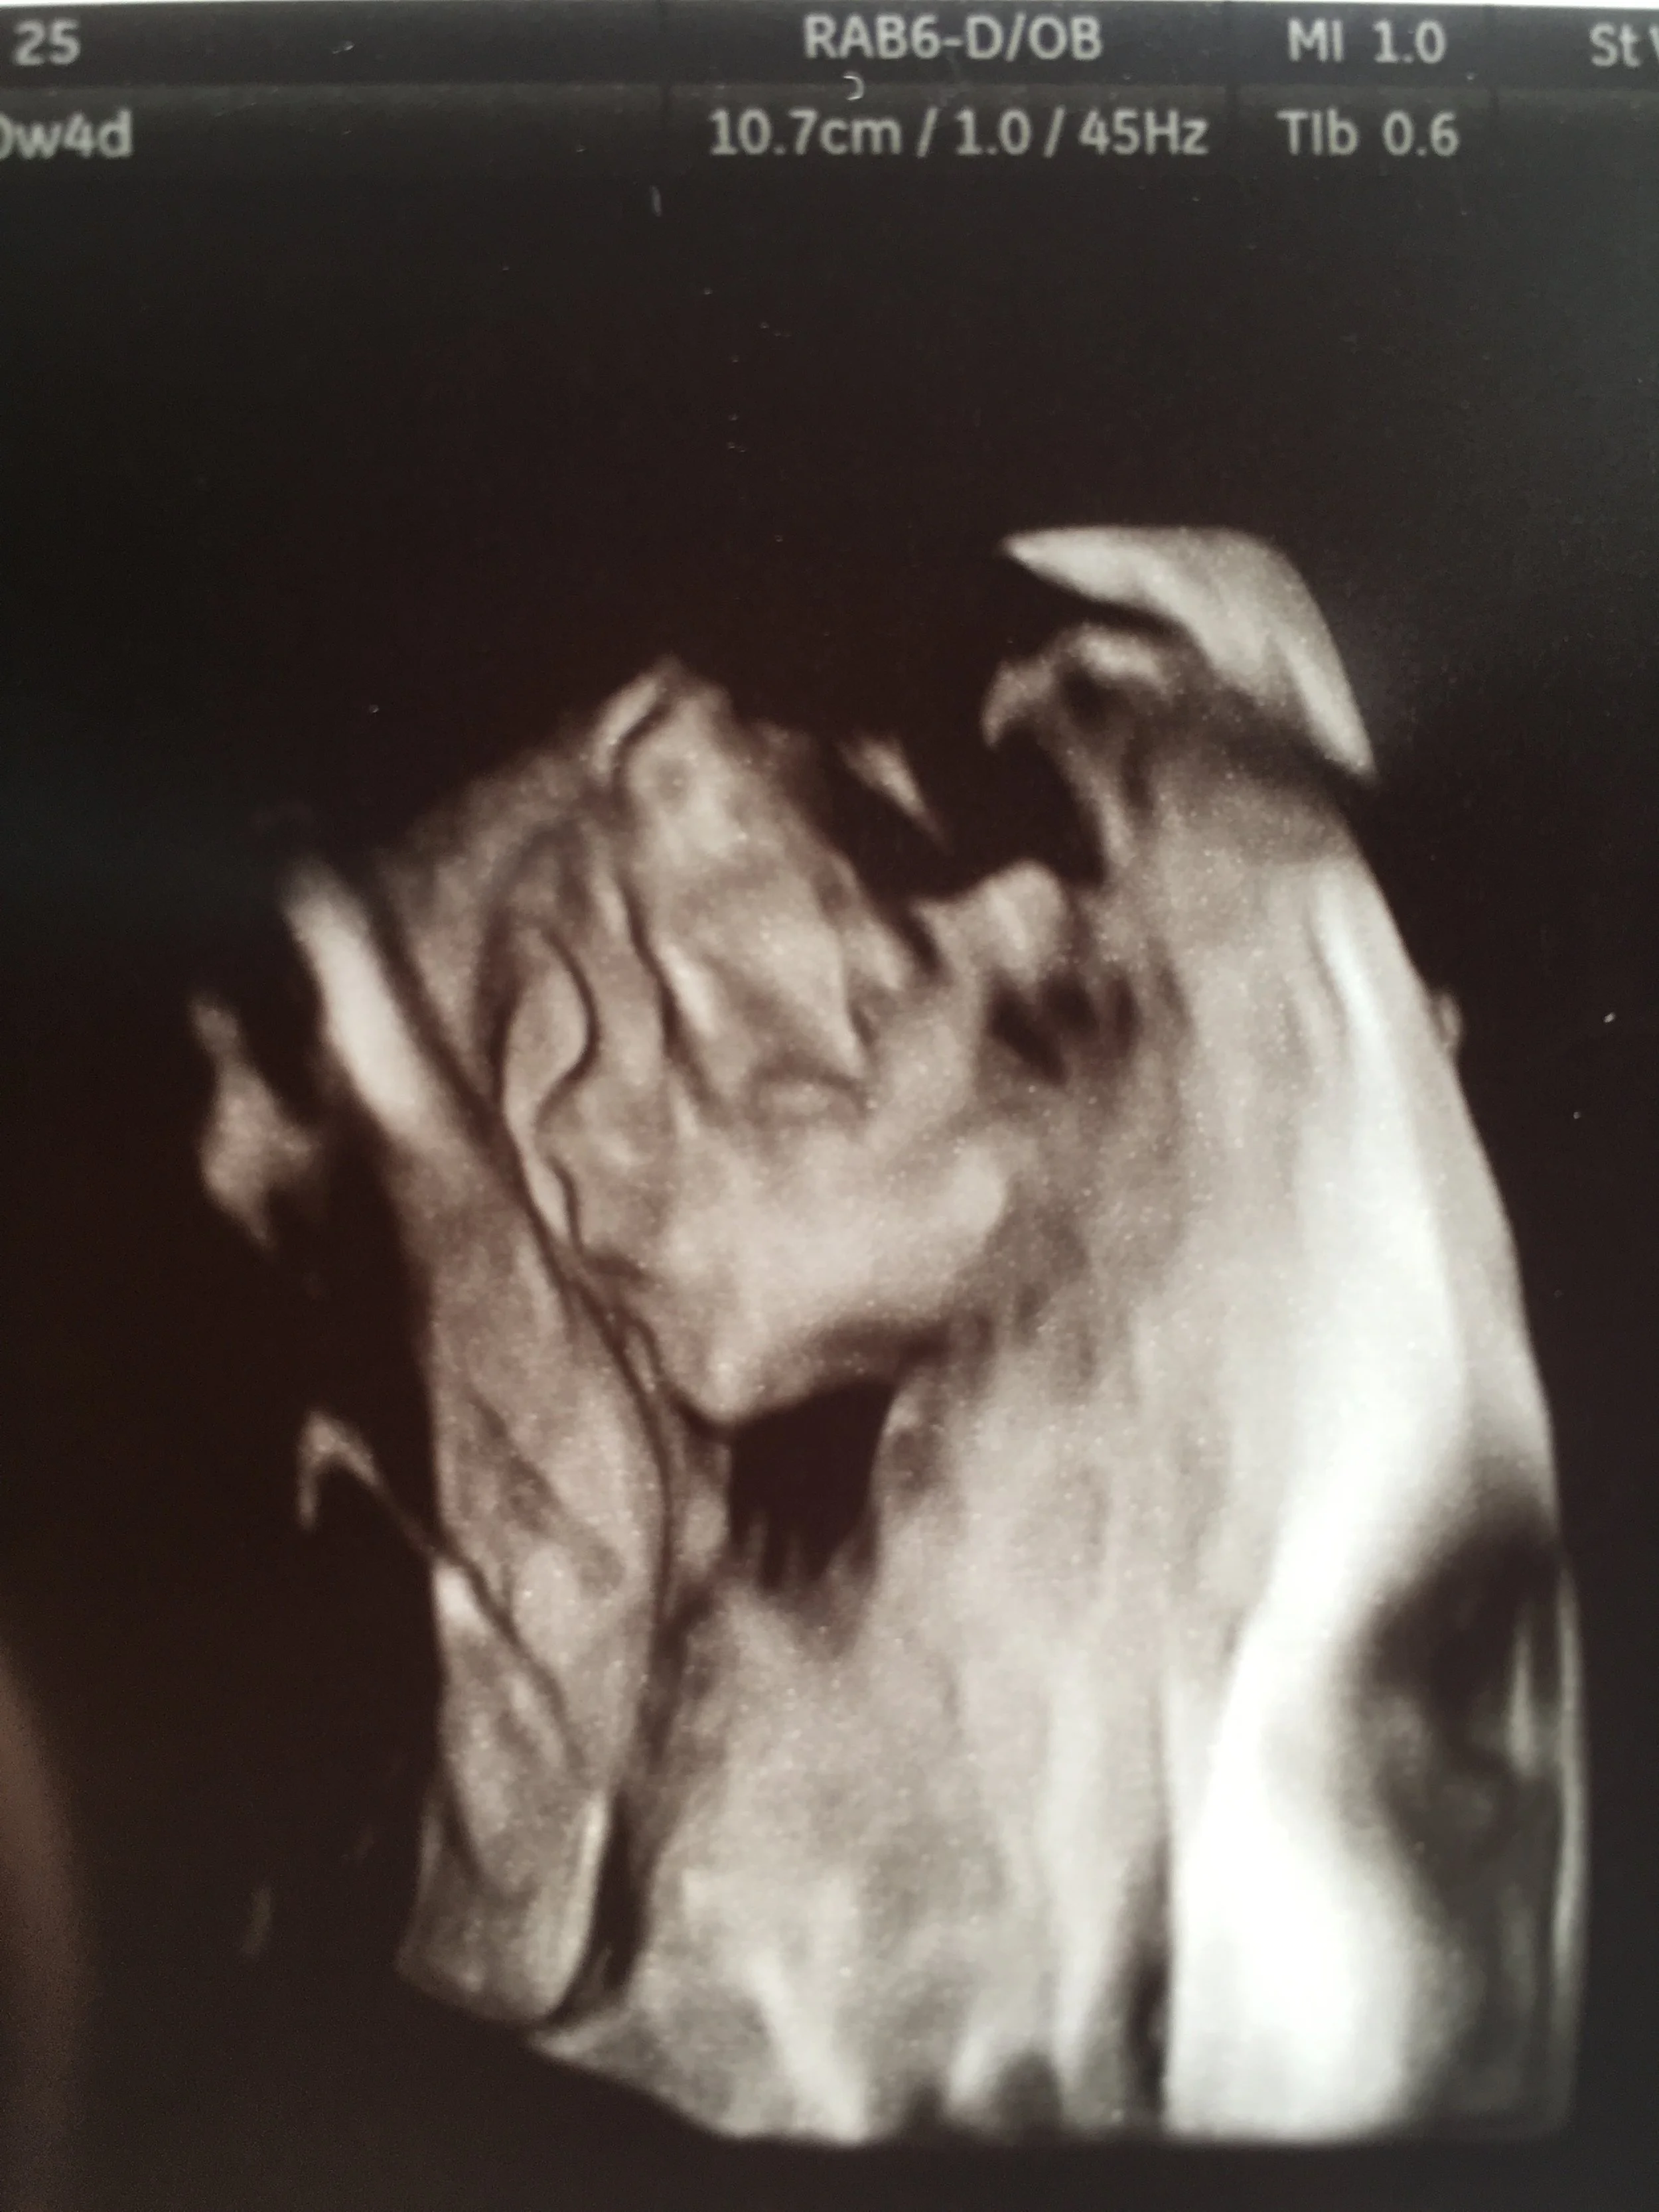

a few of my favorite moments so far | finding out that baby is a GIRL, witnessing the look on my husband's face when he felt her soft kicks for the first time,  seeing the details of her face at our 20 week anatomy scan, designing her nursery, and teaching Pier how to become a big brother. He has a baby doll that he's starting to become more and more attached to.  Currently his favorite game is for mama to rock the baby doll and sing "rock-a-bye baby"...Then Pier takes her, gives her a pat and throws her on the ground with a big enthusiastic "UH OH".  It's pretty cute.  And a bit violent.  But mostly cute.

I MEAN LOOK AT THAT SWEET FACE! Can't wait to snuggle her earth side.  She still doesn't have a name yet...but we're working on it.  Girl names are easy to pick because I love so many of them, but at the same time we can't decide on one because, well, we love so many of them.  I keep asking Jesus to name her for me.  20 more weeks to figure it out!